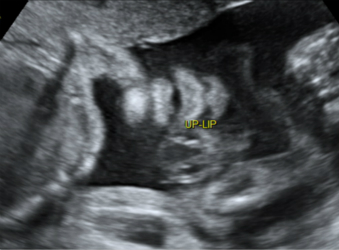

2.妊娠18周~24周超声检查:主要进行胎儿结构畸形的系统筛查。此时期胎儿各器官已发育成熟,系统产前超声检查可记录胎儿各器官结构包括头颅、面部、胸腹腔、心脏、肝脏、双肾、肢体及胎盘等结构,可发现大多数胎儿结构畸形。此阶段是观察胎儿结构和诊断胎儿畸形黄金时段,我们建议所有孕妇在此阶段务必接受一次超声检查。